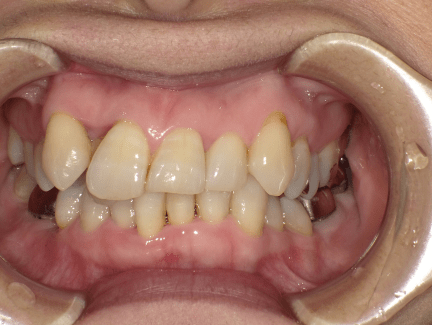

叢生がある方ですと、歯磨きが難しいのでお口の中をきれいにするのに多くの時間を必要とします。ご自身の歯磨きが難しい部分を理解して、毎回時間をかけてきれいにしていただければよいのですが、それができませんと叢生の部分は不潔になりやすく、虫歯や歯周病に罹患しやすくなってしまいます。

また、叢生部分ではかみ合わせが均等でないことが多いため特定の歯だけがすり減って歯の形がいびつになったりしてしまうこともあります。

矯正治療では歯の形を変えることはできませんので、歯のすり減りが原因で矯正治療後でも歯の高さが合わない場合には、被せ物の治療などが必要になる場合があります。